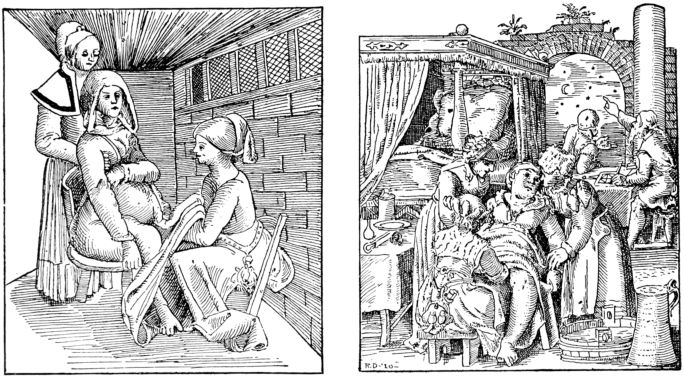

| 81. | Old prints showing early methods of delivery | 261 |